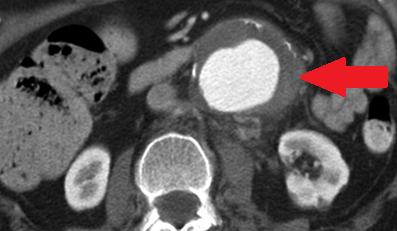

Αμφοτερόπλευρη αυτόματη νεφρική αιμορραγία — κοκκιωμάτωση Wegener (Ευγενική παραχώρηση Dr. V. Penopoulos)